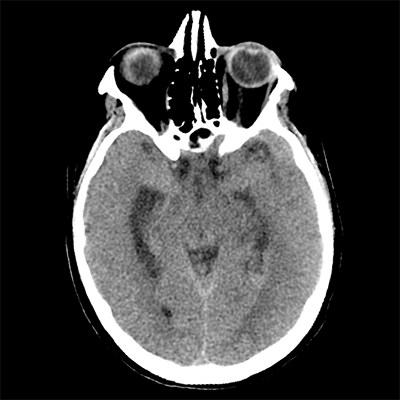

You arrive at the patient's room. You quickly examine her. Her left pupil is truly dilated and unreactive. Her right pupil is also dilated and unreactive, and also deviates to the right. She is unable to follow commands but is moving her extremities spontaneously. The right side of her body seems to be moving slightly less than her left. You escort the patient with RRT and your neurology colleague to radiology, where a non-contrast head CT and CTA head/neck are obtained.

HCT part 1 HCT part 2 HCT part 3

The non-contrast head CT looks generally similar to her prior scan. There's no new hemorrhage anywhere. There's no mass effect causing midbrain compression. The vessel imaging also looks unrevealing-- a slightly hypoplastic right A1 segment, but no clear LVO in either the anterior or posterior circulation. There's no vasoconstriction.